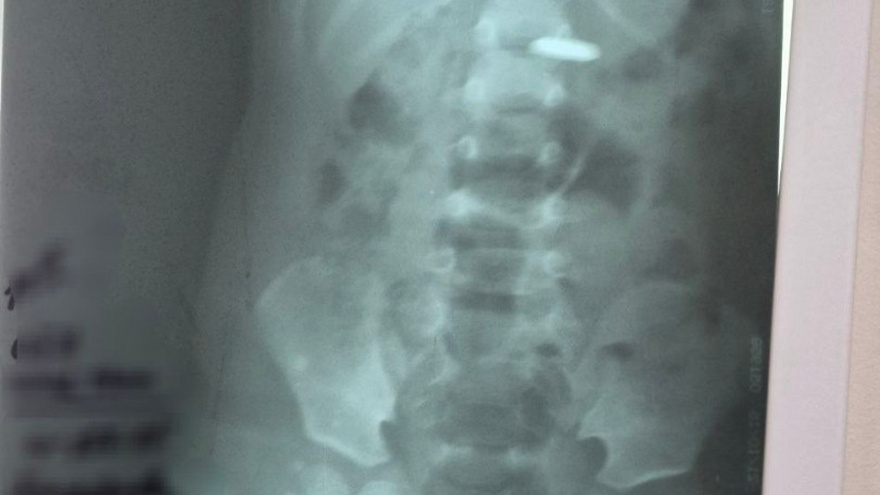

В городе Балаково Саратовской области врачи пришли на помощь годовалому малышу, который проглотил батарейку. Об этом сегодня рассказали в Балаковской городской клинической больнице, не уточнив, когда происходили события. Отмечается, что врачи вытащили батарейку из желудка с помощью эндоскопа – прибора для осмотра внутренних органов. Как сейчас себя чувствует пациент, в медучреждении не уточнили. В больнице напомнили, что проглоченная батарейка вызывает ожог.